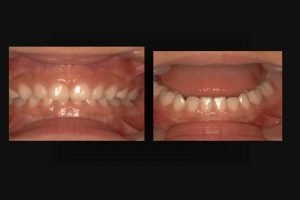

最近、乳歯の過蓋咬合の小児が増加しているような気がしてならない。(図1)

図1

図1:最近、乳歯の過蓋咬合が目立つ。